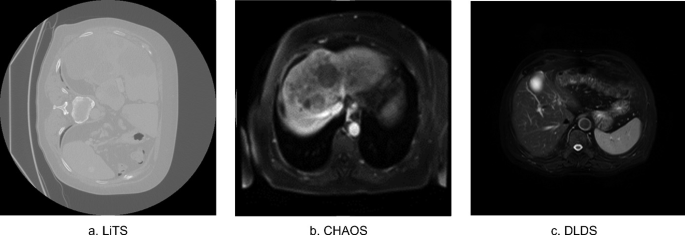

Liver diseases cause up to two million deaths yearly. Their diagnosis and treatment plans require an accurate assessment of the liver structure and tissue characteristics. Imaging modalities such as computed tomography (CT) and Magnetic resonance (MR) can be used to assess the liver. CT has better spatial resolution compared to MR, which has better tissue contrast. Each modality has its own applications. However, CT is widely used due its ease of access, lower cost and a shorter examination time. Liver segmentation is an important step that helps to accurately identify and isolate the liver from other organs and tissues in medical images. This can be useful for diagnosing and treating liver diseases. Manual liver segmentation is costly and time-intensive. Machine learning and deep learning algorithms can be used to automate this process. However, deep learning methods require a large amount of training data, which is not available for MR. There are many CT datasets available compared to few MR datasets. The use of transfer learning can help to mitigate the problem of having a small amount of training data. We suggest training a U-Net deep learning model on the large publicly available CT dataset liver tumor segmentation challenge (LiTS), then use transfer learning to fine-tune the model to the smaller available MR datasets Duke liver dataset (DLDS) and Combined (CTMR) Healthy Abdominal Organ Segmentation (CHAOS). This allows the model to leverage the knowledge it has gained from the larger CT dataset to improve its performance on the smaller MR datasets. The model reached a dice of 0.83 on unseen DLDS data after fine-tuning to the small CHAOS dataset. It also improved the testing dice on CHAOS itself when compared to training the model from scratch on CHAOS only from 0.59 to 0.86. A universal model trained on the combined datasets achieved a testing dice of 0.928 on LiTS, 0.865 on DLDS, and 0.815 on CHAOS. © The Author(s), under exclusive license to Springer Nature Switzerland AG 2024.